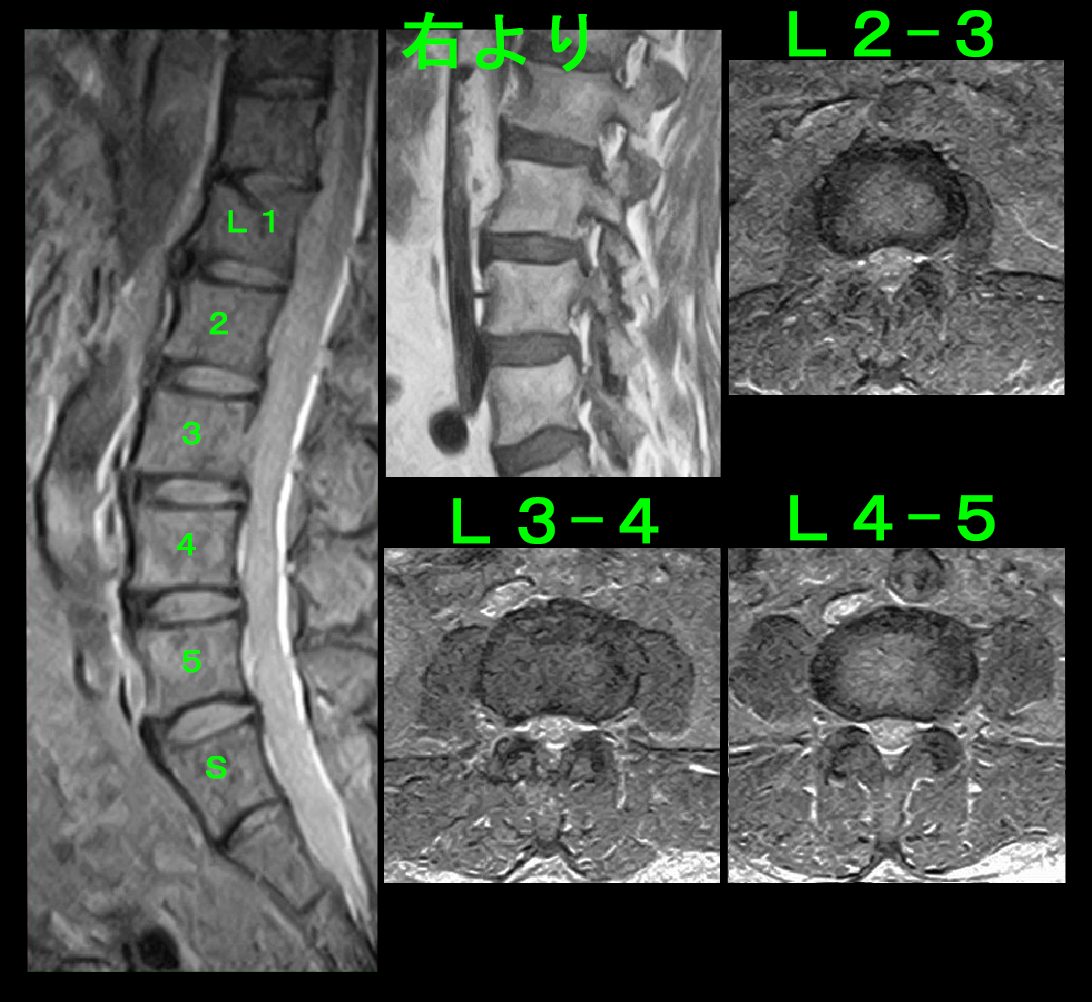

それ以外にも変形性膝関節症にみられる理学所見(視診や触診でえられる所見です)は確認されず、またレントゲン像も正常で、当初私は腰椎に起因する膝痛ではないかと推察しました。

68才女 MRLW2.jpg

しかし、腰椎のMRI検査でもそのような異常は確認されず、次に膝関節MRI検査を施行しました。